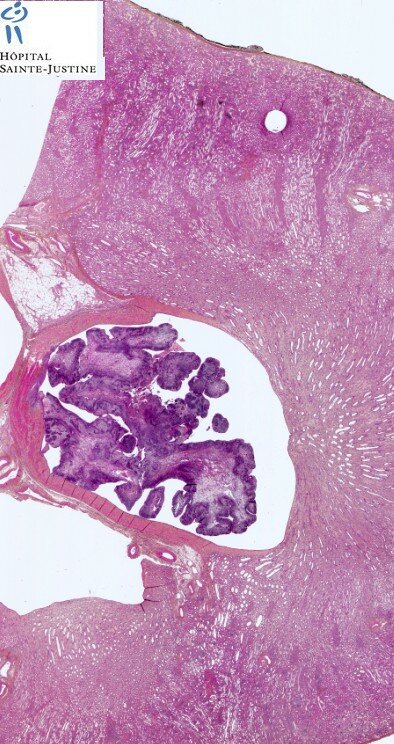

botryoid Wilms tumor

Wilms tumor

(nephroblastoma)